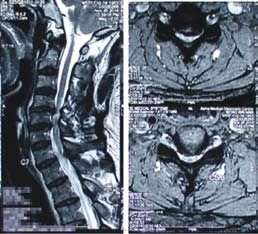

55歳的陸先生是位工程師,在2016年11月來求診,兩年來他手部 麻木 痺痛,尤其是右手拇指及二指,後來更出現 手部乏力 、走路時 腳軟 無力的情況。兩年來看了不同科的西醫及中醫,亦接受了 物理治療 及 脊醫 的保守治療。臨床的神經反射檢查顯示陸先生有頸椎中樞神經嚴重受壓的可能,隨後的 磁力共振 醫學造影確診了頸椎第四、五及第五、六節出現嚴重退化及 椎間盤突出 ,而且嚴重壓向脊髓中樞神經,脊髓神經有變形、扁平及 水腫 現象。

陸先生最後聽從醫生的醫學意見,入院進行了四小時的神經外科微創手術 ─ 頸椎前路椎間盤切除及椎體融合術,手術目的是為脊髓中樞神經減壓及鞏固頸椎的穩定性。手術後陸先生臥床休息一晚,第二天早上他發現四肢已經沒有麻木痺痛的感覺,四肢肌肉力度亦有明顯改善。在醫生的監察下他下床走動,發覺雙腳站立地面上時的感覺比手術前實在而且穩健得多,走起路來雙腳力度及步履明顯進步同時相當平穩。從 X-光 及 磁力共振 觀察,頸椎第四、五及第五、六節脊髓受壓程度已大大改善。陸先生當天下午,即手術後24小時便出院回家了。